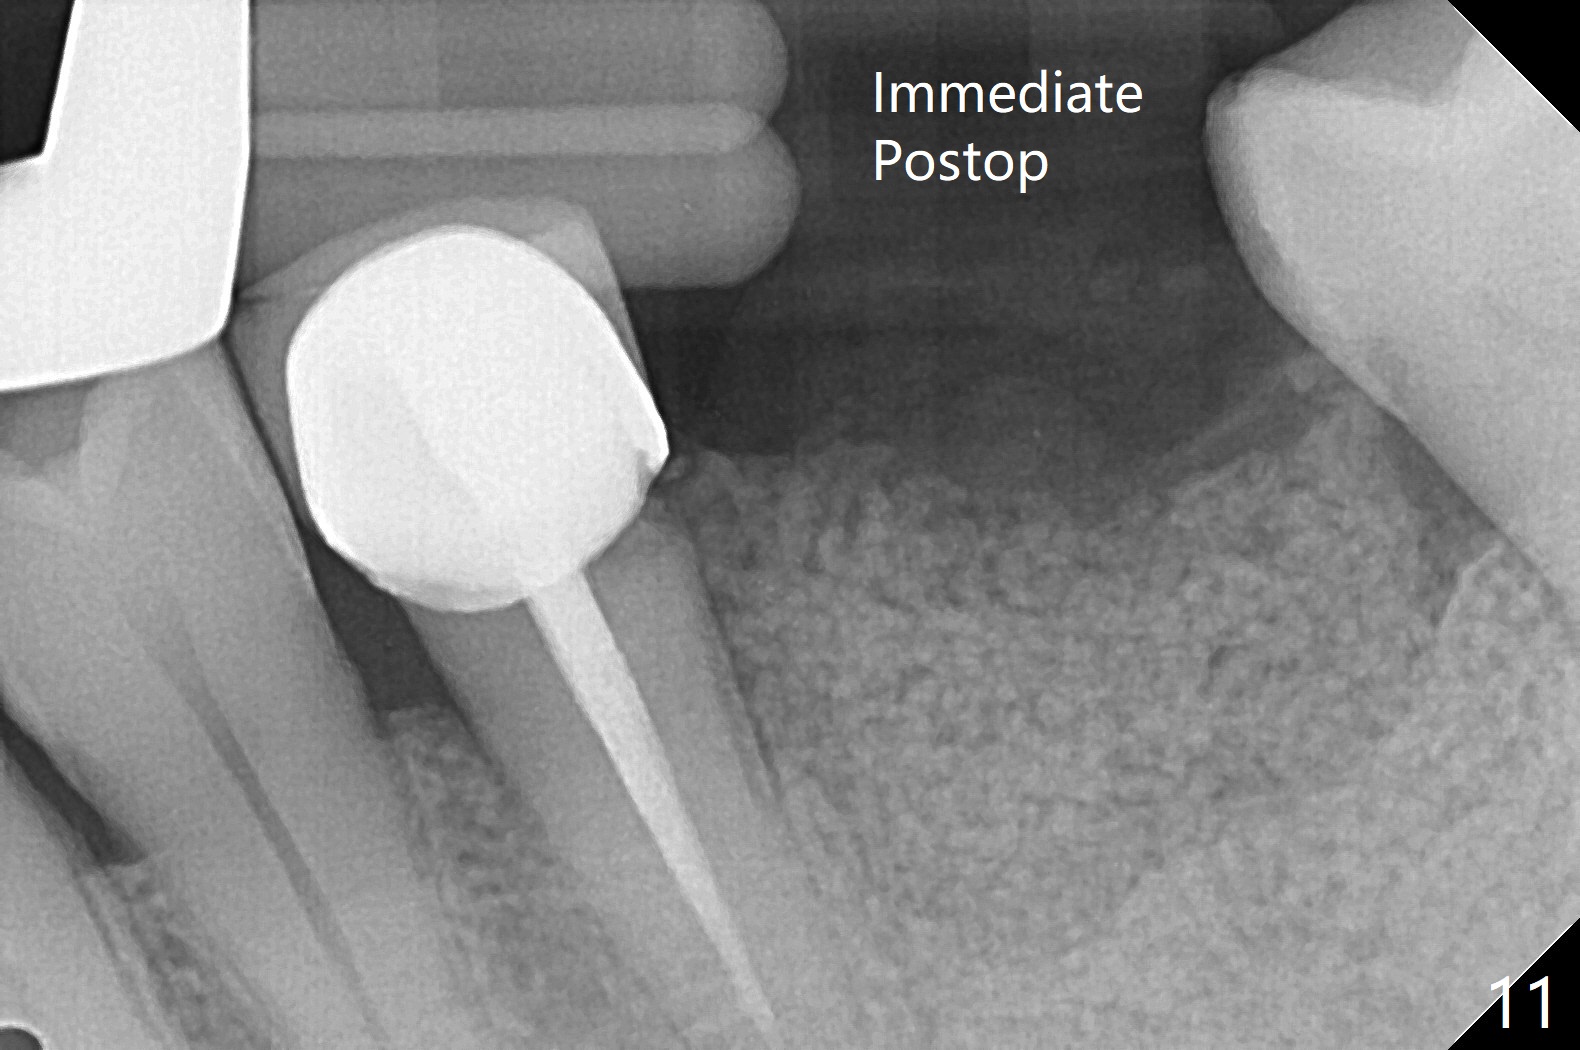

A 54-year-old man has distal (D) root fracture at #19 while the implant at #2 is osteointegrarting (Fig.1,2). Because of the large distal defect (Fig.3, after extraction), osteotomy (red line) will be initiated in the mesial socket (Fig.4, as distal as possible, with the coronal end in the middle of the socket) or the mesial slope of the septum (Fig.5) so that the implant (green) will be supported by the distally displaced septum (Fig.6 arrow). CT taken 8 months later confirms distal root fracture. A 6x11.5 mm or longer implant seems to be appropriate for the site (Fig.7). Three years later there is severe buccal swelling (Fig.8) with vertical mesial and distal root fractures (Fig.9). Although the buccal plate is lost, the septum remains (Fig.10 S), which will provide with blood supply to the bone graft (Fig.11), covered with Bioxclude and 6-month membrane and PSA suture. The bone density in the mesial and distal sockets is higher than that in the septum 8 months post cortical bone graft (Fig.12). In spite of bone graft, the buccolingual width reduces by almost 4 mm 8 months post extraction (Fig.3,4). In spite of bone graft, the buccolingual width reduces by almost 4 mm in 8 months post extraction (Fig.3,4). A 5x11.5 mm implant will be placed (Fig.15).